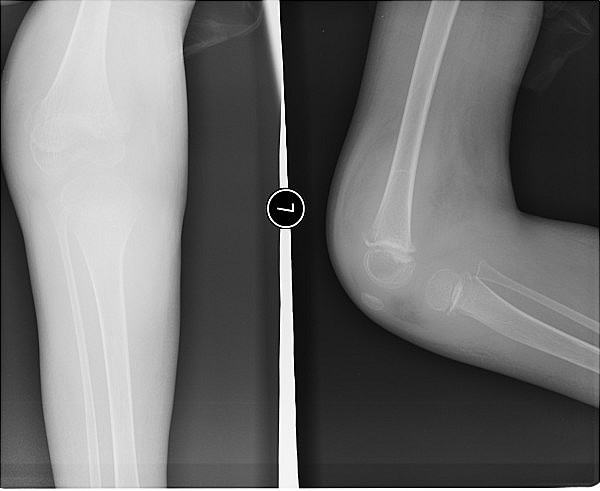

标题: PED0878:男.6岁,脑瘫患者.双下肢肿胀,以右膝关节显著. [打印本页]

标题: PED0878:男.6岁,脑瘫患者.双下肢肿胀,以右膝关节显著.

主要是关节积液、骨质疏松。

关节软组织肿胀,考虑关节积液,

关节肿胀,骨质疏松,结合临床考虑夏科关节早期改变

关节肿胀,骨质疏松。考虑神经性关节病。

关节周围软组织肿胀,密度增高,胫骨骺有半脱位,结合病史,考虑-神经关节性病